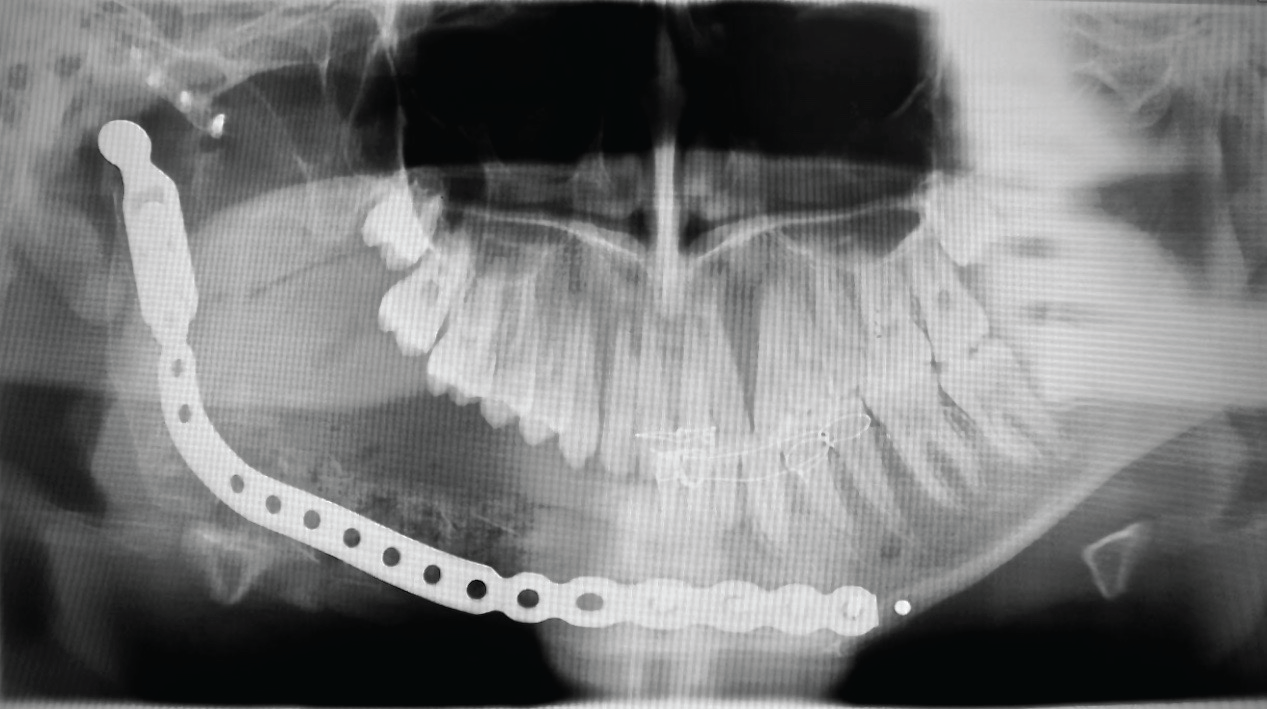

Figure 3: Post-operative (4 weeks) OPG showing a reconstruction plate with early and immature bone graft. View Figure 3

Figure 4: Post-operative (12 months) OPG depicting a now mature ossicle ready to receive dental implants and rehabilitation of the dentition. View Figure 4

A 17-year-old male patient presented with right-sided facial asymmetry, and a large bony mass that was painless could be palpated in the lower jaw. The teeth of the involved hemi-mandible were mobile, and there was paraesthesia of the distribution of the lower right inferior alveolar nerve. The patient presented with no systemic compromise, and was otherwise well. A benign neoplasm (Ameloblastoma) was suspected and confirmed via incisional biopsy of the right hemi-mandible (Figure 1). A right-sided hemi-mandibulectomy with disarticulation, was subsequently performed via an intra-oral and pre-auricular approach. A preformed reconstruction plate with add-on condyle (DePuy Synthes CMF, West Chester, PA) was used together with an alloplastic Temporomandibular joint (TMJ) fossa (Zimmer Biomet CMF, Jacksonville, FL) (Figure 2). An allogenic demineralised humerus (Bone SA, Bramley, Johannesburg, South Africa) was used as a conduit for a compacted autogenous PCCB graft, harvested from the anterior iliac crest. This bone conduit was then secured to the reconstruction plate (Figure 3) and the intra-oral access closed in two layers. Maxillomandibular fixation (MMF) was applied (released after 4 weeks), and a nasogastric feeding tube (NGT) inserted. The Patient was fed for seven days via NGT and was kept on antibiotic prophylaxis and analgesia for that duration, and then discharged from hospital. Follow-up occurred at regular intervals for 18 months after the surgery (Figure 4).